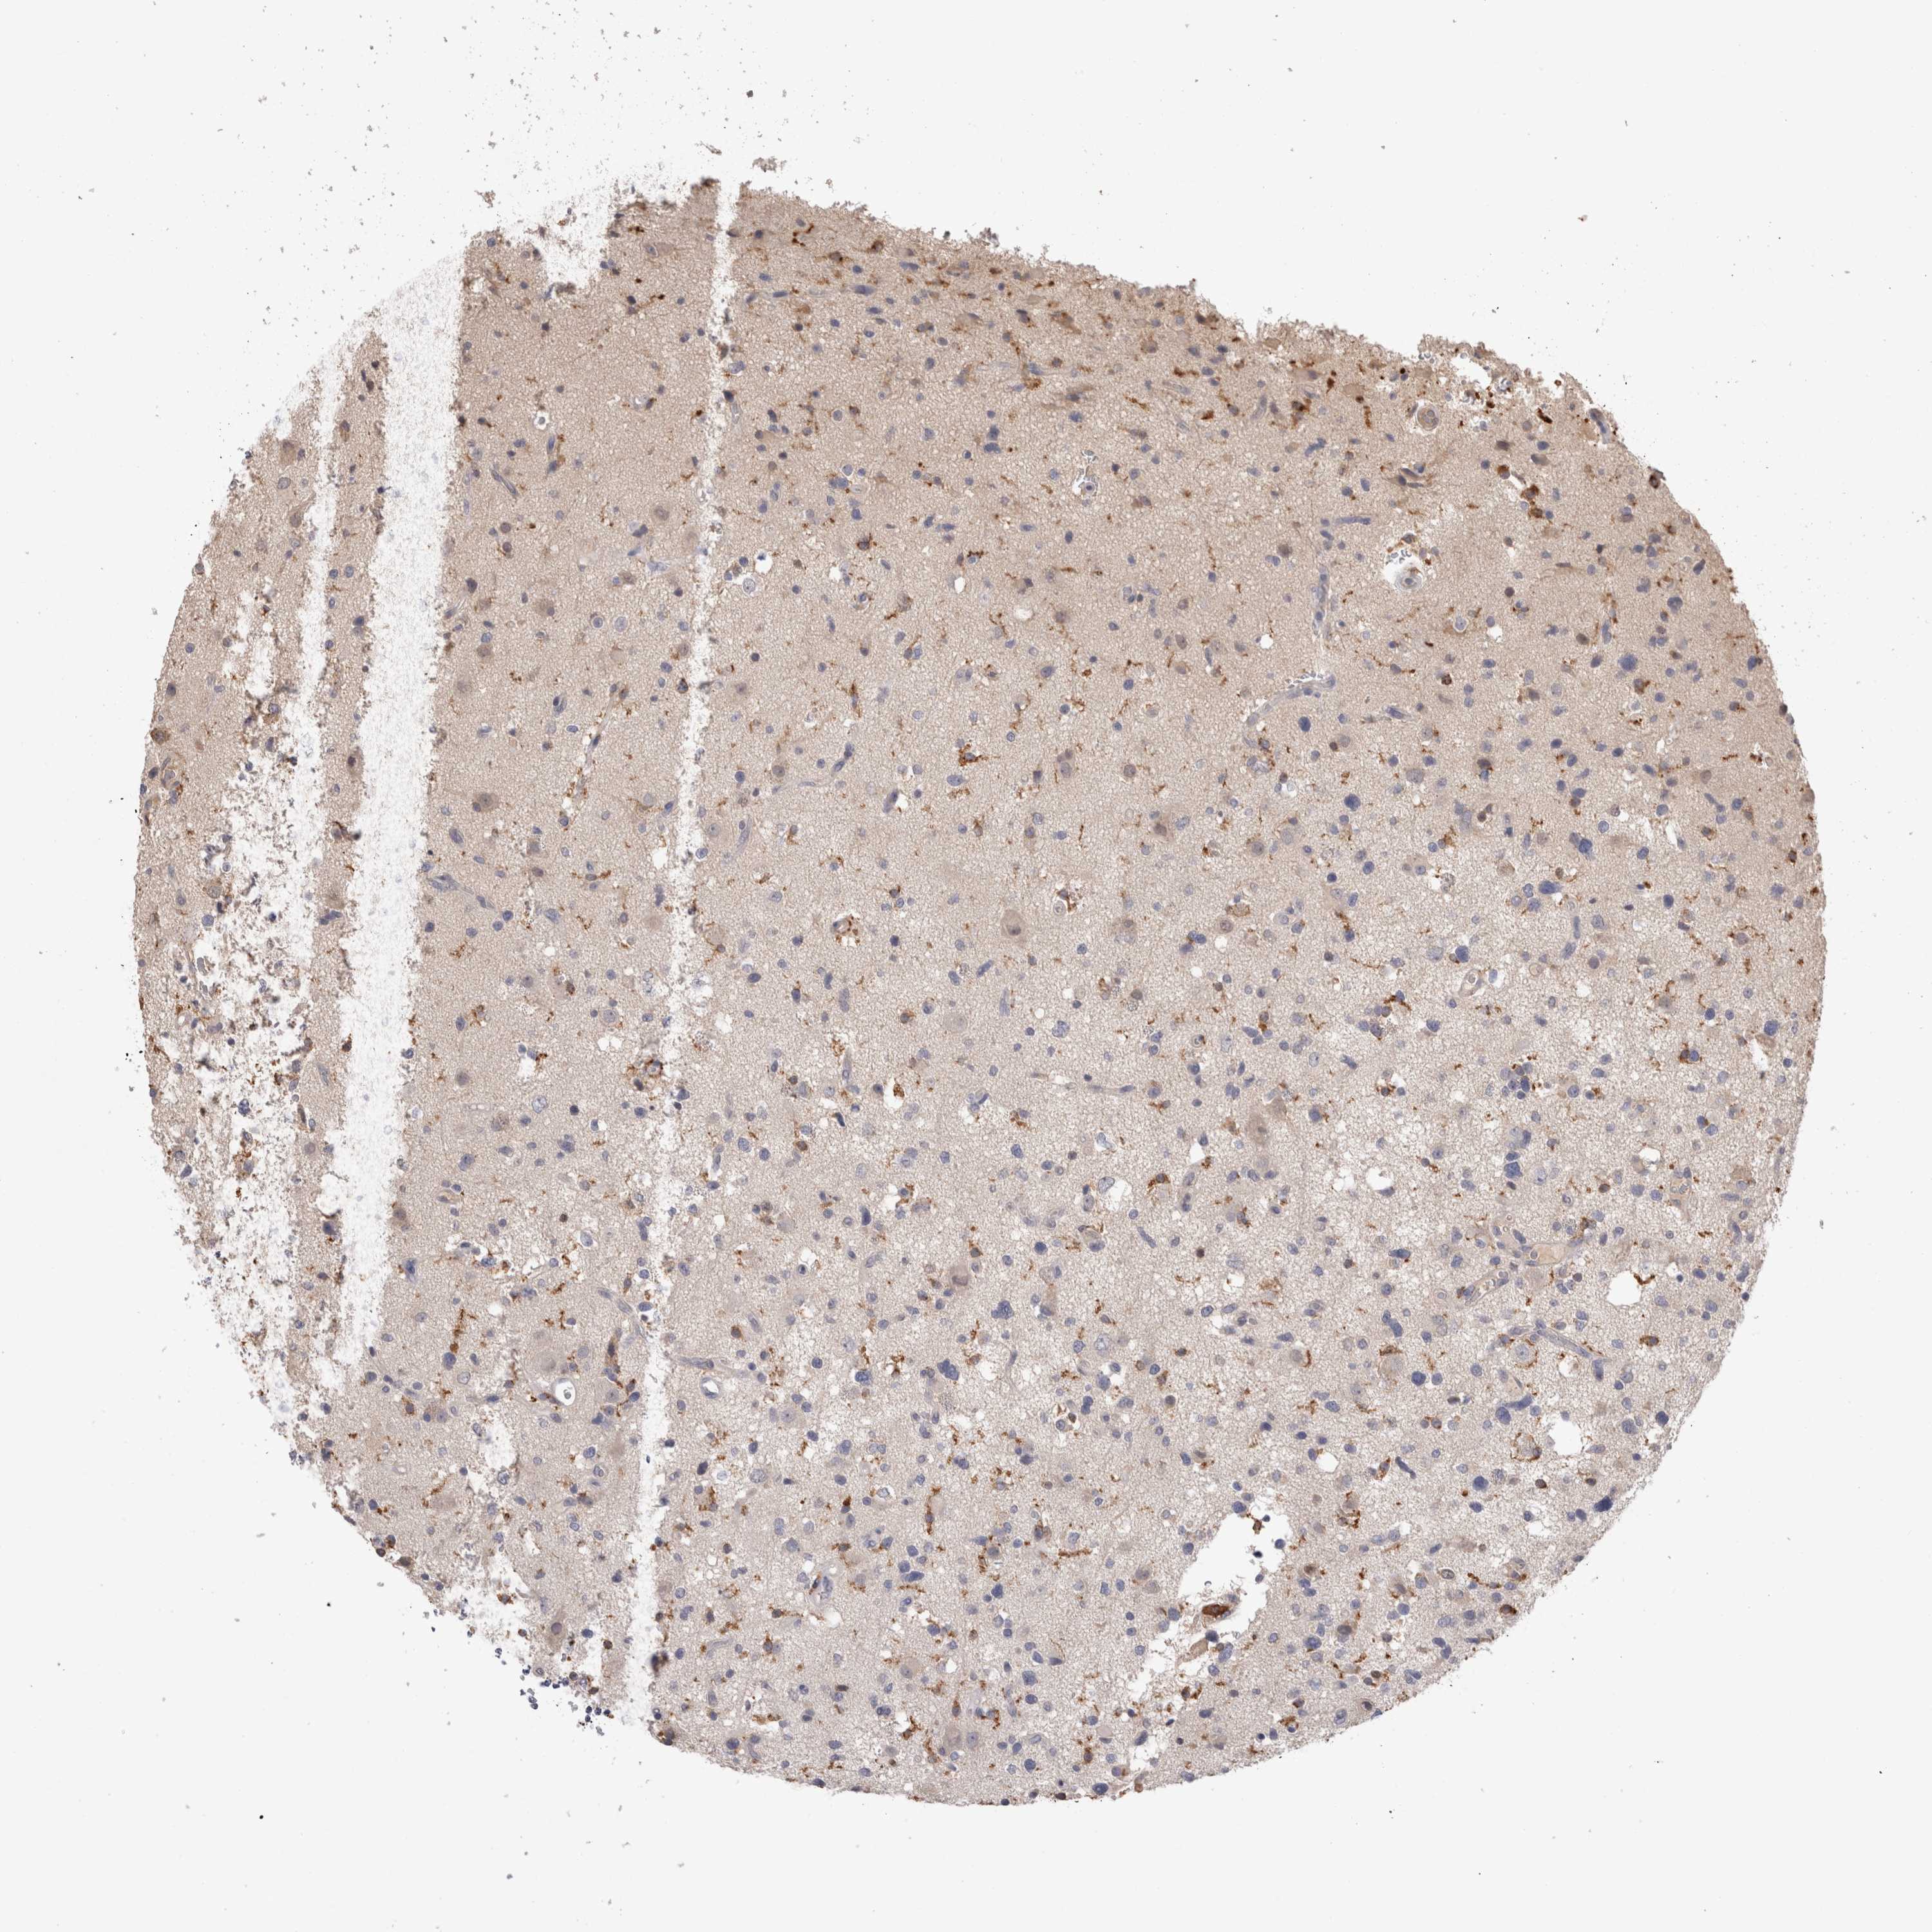

GLIOMA - Protein expressioni

A mouse-over function shows sample information and annotation data. Click on an image to view it in a full screen mode. Samples can be filtered based on level of antibody staining by selecting one or several of the following categories: high, medium, low and not detected. The assay and annotation is described here.

Note that samples used for immunohistochemistry by the Human Protein Atlas do not correspond to samples in the TCGA dataset.

Antibody stainingi

Antibody staining in the annotated cell types in the current human tissue is reported as not detected, low, medium, or high, based on conventional immunohistochemistry profiling in selected tissues. This score is based on the combination of the staining intensity and fraction of stained cells.

Each image is clickable and will lead to virtual microscopy that enables deeper exploration of all samples and also displays staining intensity scores, fraction scores and subcellular localization as well as patient and tissue information for each sample.

Antibody HPA003903

Antibody HPA072756

Antibody CAB026000

Staining

High

Medium

Low

Not detected

Intensity

Strong

Moderate

Weak

Negative

Quantity

>75%

75%-25%

<25%

None

Location

Nuclear

Cytoplasmic/membranous

Cytoplasmic/membranous,nuclear

Glioma, malignant, High grade

Glioma, malignant, NOS

Glioma, malignant, Low grade